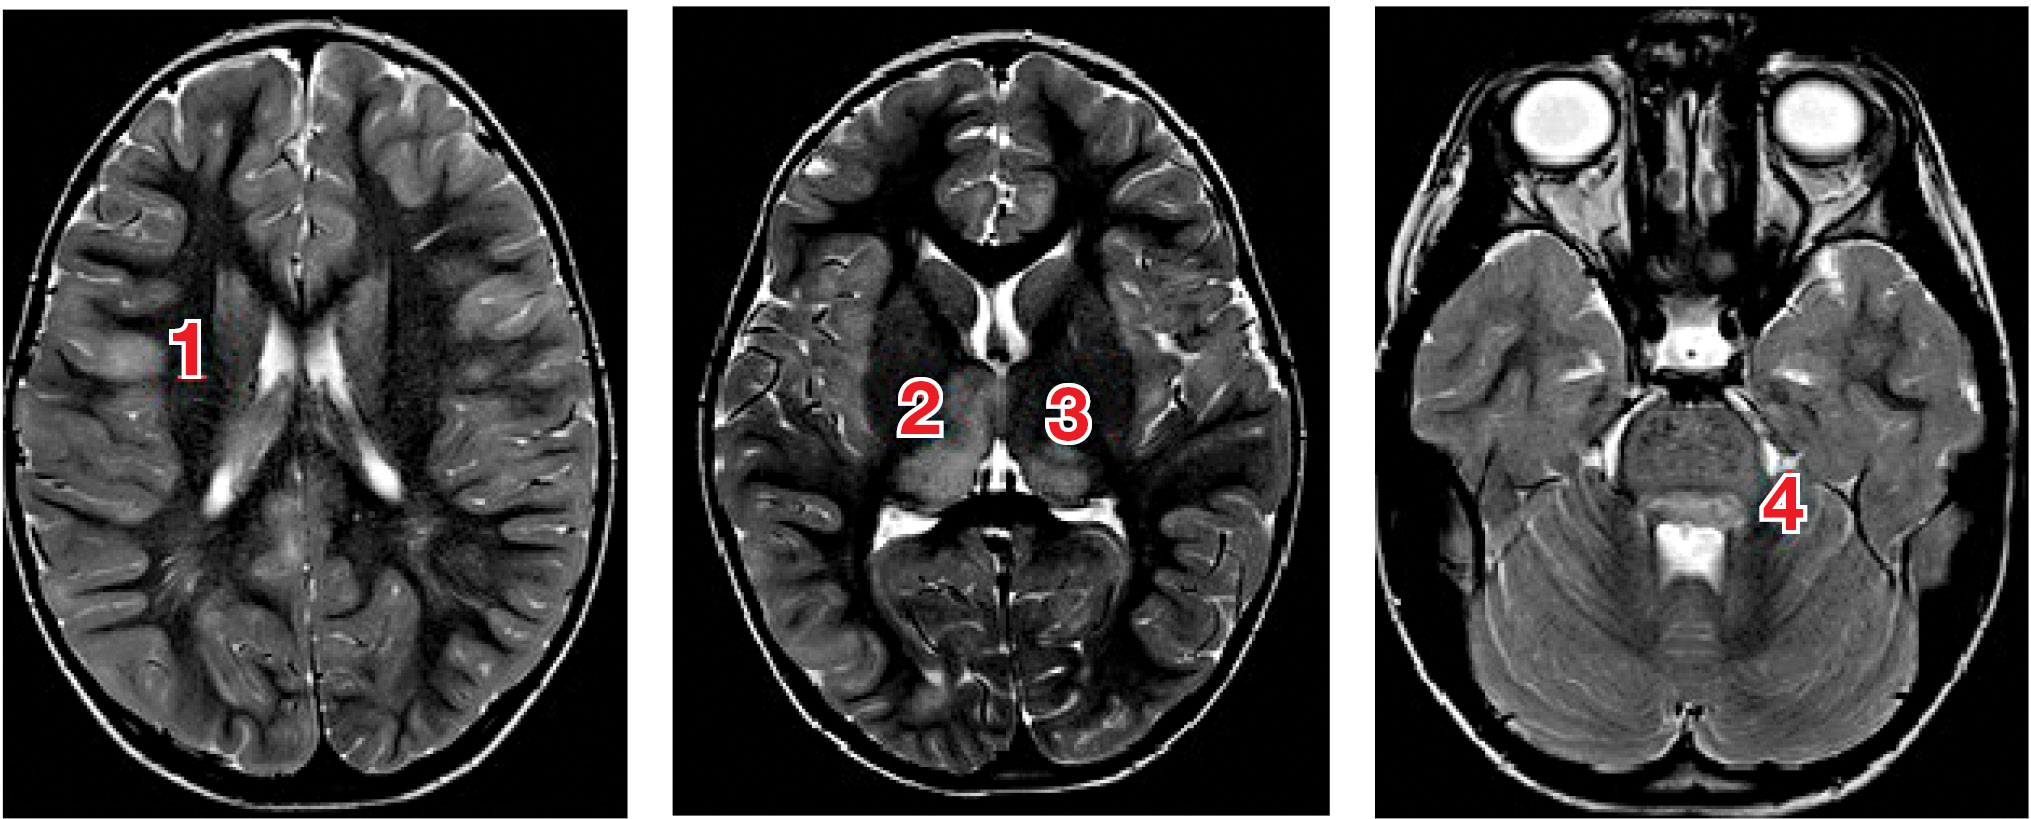

При оценке прогностической ценности структурной МРТ и данных DTI и МРС у пациентов с энцефалитом типа LGI1 (leucin-rich glioma-inactivated 1 protein) было установлено, что в остром периоде на структурной МРТ изменений где-либо, кроме височных долей, не выявлено; по данным DTI регистрировались широко распространенные изменения белого вещества полушарий и мозжечка со снижением по данным МРС уровня глутамина и глутамата [18]. Прогностически значимыми, с точки зрения исходов, оцениваемых по шкале Рэнкина и по шкале когнитивного дефицита Адденбрука, оказались объем сохранного серого вещества и степень дезинтеграции трактов в белом веществе. При рабическом энцефалите, ВИЧ-ассоциированной лейкоэнцефалопатии, японском энцефалите и энцефалите, вызванном вирусом Эпштейна–Барр, также сообщается о значительно более широком спектре поражения головного мозга, выявляемого с помощью DTI, по сравнению с таковым по данным структурной МРТ [19–22]. Пример изменений, выявляемых с помощью структурной МРТ при энцефалитах у детей, представлен на рис. 1.

Рис. 1. МРТ головного мозга пациентки Х., 4 года: энцефалит цитомегаловирусной этиологии, острый период заболевания

Примечание. На МРТ в последовательностях Т2 и FLAIR выявляются очаги воспаления в коре (1), таламусах (2, 3) и стволе мозга (4) (собственные данные).